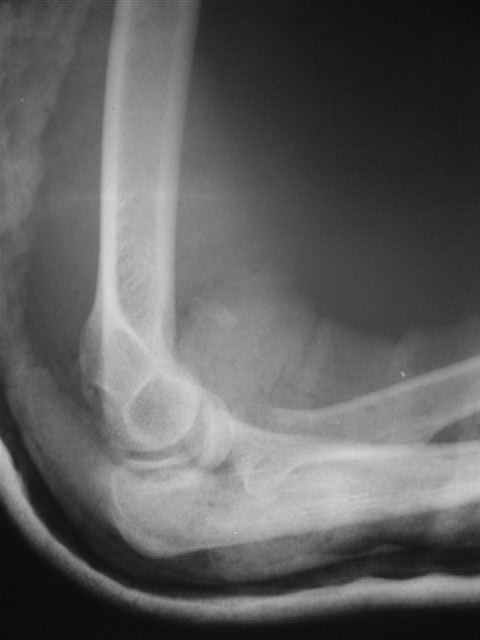

Вывих костей предплечья и перелом головки лучевой кости. |

Уважаемые коллеги!Помогите с источниками литературы по вопросу о сроках резекции головки лучевой кости и гетеротопической оссификации после вывиха костей предплечья. Необходимо ответить на жалобу, где больная просит возместитьматериальные затраты на лечения с лечащих врачей, которые участвовали влечении с 4.09.04 по 10.11.04, объясняет, что врачи нарушили стандарты леченияи поздно направили на оперативное лечение.История болезни, женщина 46 лет упала дома 4.09.04, получила заднелатеральныйвывих костей предплечья и перелом головки лучевой кости, под местной анестезиейвывих вправлен, на контрольной рентгенограмме соотношение отломков головкилучевой кости расценено, как удовлетворительное. Наложена задняя гипсовая шина.Лечение: холод, кетанов 3 дня, магнитотерапия, ЛФК пальцев, рентген контрольчерез 7 дней, с 8.09.05 наклофен 50 мг 2 раза в день. 11.09.04 на контрольной рентгенограмме состояние отломков прежнее. 30.09.04. Гипсовая шина снята через 26 дней. Лечение: ЛФК, массаж, электрофорезлидазой.9.10.04. В левом локтевом суставе сгибание 80, разгибание 120.19.10.04. Сгибание 80, разгибание 140, ротационные движения в пределах 10 гр.28.10.04. Сгибание 80, разгибание 150, ротационные движения в пределах 10 гр.10.11.04. На рентгенограмме локтевого сустава отмечается гетеротопическаяоссификация.Учитывая неэффективность консервативного лечения, больная направлена на оперативноелечение.Больная по собственным каналам уехала в г. Киев, где произведенарезекция головки лучевой кости, после операции развился неврит лучевого нерва.На данный момент больная продолжает лечение у нейрохирурга.-- С уважением,Анатолий Борзунов

А есть снимки?

Во время встречи фотоаппарата не было, забрать снимки на время, муж больной снимки не разрешил.